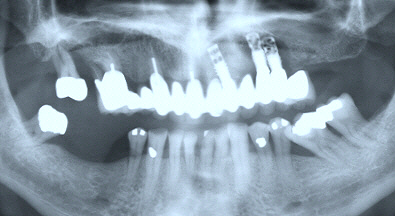

(上顎ブリッジの動揺を主訴として来られましたが、インプラント周囲の骨吸収が著しく、除去する必要があります)